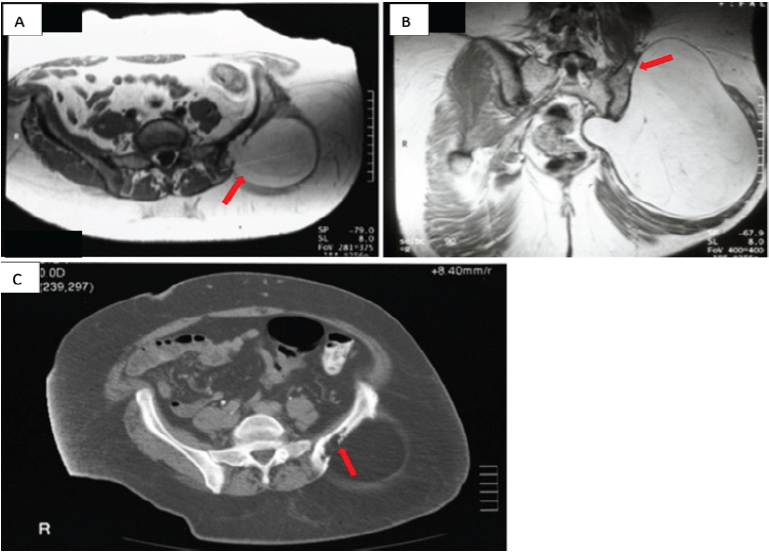

A 57-year-old female presented with a 1-month history of a progressively enlarging mass and pain in her left buttock. The pain was worse with activity but also present at rest. She required analgesic medications for relief of her symptoms. There was no history of antecedent trauma and she denied paresthesias or weakness in the affected lower extremity. She had no bowel or bladder dysfunction and reported no constitutional symptoms or weight loss. On physical examination, there was a large, slightly firm, and non-tender mass occupying nearly the entire left buttock. There were no changes in the skin overlying the mass and examination of the spine revealed no deformity or focal tenderness to deep palpation. She had a full painless, active, and passive range of motion in her lumbosacral spine and hips. She had no neurologic deficit in either lower extremity and her vascular examination was normal. Anterior-posterior (AP) pelvis radiographs showed no apparent osseous abnormality. A technetium-99m pyrophosphate bone scintigram demonstrated no abnormal focal uptake in the involved area. Magnetic resonance imaging (MRI) showed a large lobulated mass in the left buttock abutting the ilium with a homogenous and hyperintense signal on both T1 and T2 axial and coronal images. There was a focal area of hyperintense signal penetrating the outer table of the ilium and replacing the marrow; the inner table was intact (Fig. 1a). Tumor extension into the left sciatic notch was also seen with mild displacement of the pelvic viscera (Fig. 1b). Computed tomography (CT) of the pelvis better demonstrated osseous scalloping of the outer table of the ilium with a well-defined border between the bone and the soft tissue mass (Fig. 1c).

Figure 1: Case 1 imaging findings (a) (magnetic resonance imaging [MRI] – axial T1-weighted image) demonstrate erosion of the outer table of the ilium by a large hyperintense and homogenous fatty mass with intramedullary tumor extension (red arrow). (b) (MRI – coronal T2-weighted image) demonstrates focal erosion (red arrow) of the outer table of the ilium superiorly and extension of the tumor into the sciatic notch with medial displacement of the pelvic viscera by the soft tissue mass. (c) (Computed tomography – axial) demonstrates a large osseous erosion in the outer table of the ilium by a large low attenuation mass with some bone remodeling anteriorly (red arrow).